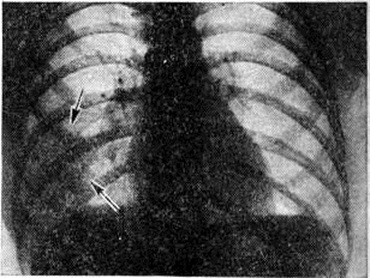

При очаговой Пневмония умеренный лейкоцитоз отмечается лишь у половины больных. Более характерны нейтрофильный сдвиг влево, ускоренная РОЭ, уменьшение или исчезновение эозинофилов. При выраженных явлениях интоксикации может наблюдаться протеинурия, микрогематурия и цилиндрурия. У больных с очаговой Пневмония снижены жизненная ёмкость лёгких и максимальная вентиляция, повышены минутный объем дыхания, отношение остаточного объёма к общей ёмкости лёгких. У 23% больных отсутствуют убедительные клинические, признаки очаговой Пневмония, и диагноз ставят на основании рентгенологическое данных.

При перкуссии часто определяют признаки острого вздутия лёгких: тимпанит, низкое расположение краёв лёгких, уменьшение абсолютной сердечной тупости. Определяют небольшое укорочение перкуторного звука соответственно зоне инфильтрации и расширение корня лёгкого на поражённой стороне. При аускультации дыхание жёсткое, выслушиваются нестойкие скудные сухие хрипы, иногда сухих и влажных хрипов много. В некоторых случаях перкуторные и аускультативные признаки выражены слабо или отсутствуют. Часто между клинические, и рентгенологическое признаками гриппозных Пневмония наблюдается расхождение. Так, при выраженных рентгенологическое признаках пневмонической инфильтрации отсутствуют её физикальные проявления или, напротив, у больных с клинически выраженными признаками Пневмония рентгеноскопически и рентгенографически определяют лишь небольшое расширение прикорневых теней и отставание экскурсий диафрагмы. По данным Н. С. Молчанова (1971), чаще других поражаются задние сегменты верхних долей, верхушечный и задний базальный сегменты нижних долей. В начале заболевания выражена тахикардия, АД несколько повышается в первые дни болезни, а затем снижается.

При синдроме Леффлера (смотри полный свод знаний Леффлера синдром) одним из частых клинические, проявлений Пневмония является сочетание инфильтратов в лёгочной ткани с эозинофилией в крови.

Пневмония могут возникать у больных с диффузными заболеваниями соединительной ткани. Ревматические Пневмония развиваются при II и III степени активности ревматизма. Для ревматической Пневмония характерны выраженная лихорадка, кашель с выделением кровянистой мокроты, боли в грудной клетке, усиливающиеся при кашле и глубоком дыхании, нарастающая одышка, тахикардия, цианоз, у некоторых больных отмечаются приступы удушья. Поражаются преимущественно нижние доли лёгких, чаще правого. Физикальные данные зависят от локализации и величины пневмонического инфильтрата. Определяются влажные мелкопузырчатые хрипы, шум трения плевры, реже укорочение перкуторного звука. При бактериологические исследовании мокрота у большинства больных оказывается стерильной, иногда из неё выделяют непатогенную и условно-патогенную флору. На ЭКГ при ревматической Пневмония выявляется нарастание признаков гипертрофии и перегрузки правого желудочка. В крови отмечается умеренный лейкоцитоз, палочкоядерный сдвиг лейкоцитарной формулы и ускорение РОЭ. Сочетание гиперкоагуляции с угнетением антисвёртывающих механизмов и сосудистыми поражениями создаёт условия для тромбообразования (гистологически в лёгких обнаруживают тромбы и кровоизлияния). Функциональные исследования органов дыхания выявляют преобладание нарушения вентиляции рестриктивного типа.